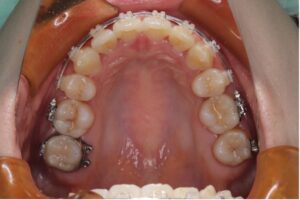

上の歯は裏側、下の歯は表側に装置をつけるワイヤー矯正です。

笑ったときに見えやすい上の歯は裏側にすることで見た目への影響を抑えることができます。

上の裏側についてる装置が舌に触れるため慣れるまで発音に違和感はありますが、フルリンガル(上下裏側)に比べると影響は少ないです。